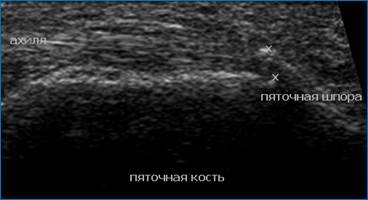

У пациентов пожилого возраста могут быть обнаружены пяточные шпоры как следствие инволютивных изменений в стопе. Это костные разрастания в виде шипа или клина в области энтезиса ахиллова сухожилия или подошвенной фасции. Подобные изменения могут быть визуализированы как рентгенологически (рис.10), так и эхографически (рис. 11).

Рис. 11. Пяточная шпора (ультразвуковая картина)